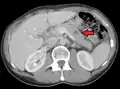

Pulmonary metastases shown on Chest X-Ray

The cells in a metastatic tumor resemble those in the primary tumor. Once the cancerous tissue is examined under a microscope to determine the cell type, a doctor can usually tell whether that type of cell is normally found in the part of the body from which the tissue sample was taken.

For instance, breast cancer cells look the same whether they are found in the breast or have spread to another part of the body. So, if a tissue sample taken from a tumor in the lung contains cells that look like breast cells, the doctor determines that the lung tumor is a secondary tumor. Still, the determination of the primary tumor can often be very difficult, and the pathologist may have to use several adjuvant techniques, such as immunohistochemistry, FISH (fluorescent in situ hybridization), and others. Despite the use of techniques, in some cases the primary tumor remains unidentified.